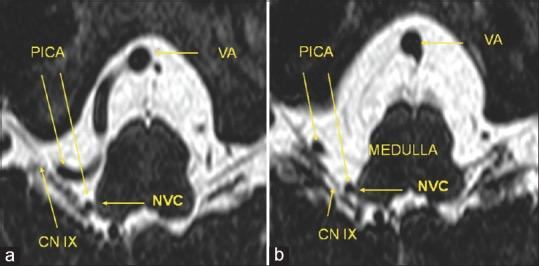

15 patients (female/male: 5/10) were examined. All of them underwent MVD (100%). Microvascular details were documented. The posterior inferior cerebellar artery (PICA) was the most common causative vessel in 12 of 15 patients (80%), the vertebral artery (VA) alone in one case (6.7%), and the combination of compression by the VA and PICA in 3 patients (13.3%). We identified three distinct types of NVC within the root entry zone of CN IX.

检查了15例患者(女性/男性:5/10)。所有患者均接受了MVD(100%)。记录了微血管细节。15例患者中有12例(80%)后下小脑动脉(PICA)是最常见的致病血管,1例(6.7%)单独由椎动脉(VA)引起,3例(13.3%)由VA和PICA联合压迫引起。我们在CN IX的神经根入区识别出三种不同类型的NVC。